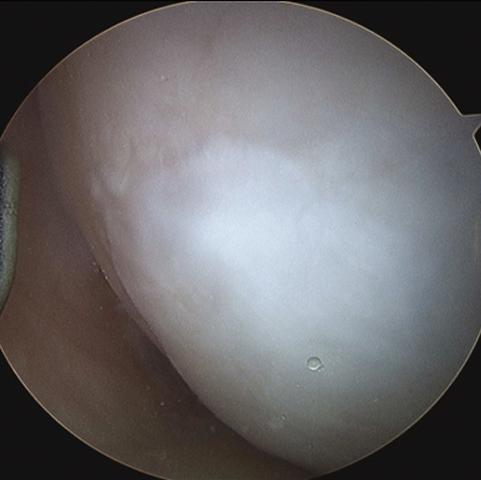

The arthroscopic images taken during a BST-CarGel surgery. The original lesion before BST-CarGel treatment.

The repaired lesion at the 13-month 2nd look arthroscopy. The delivery of BST-CarGel in a cartilage lesion.

Dr. Ranger was later involved in Health Canada’s Special Access Program where 33 patients received the new treatment, and in the international randomized controlled trial of 80 patients, Dr. Ranger operated on several patients and the effects he was able to see through arthroscopy were the highest quality of cartilage repair that he had seen in his career. He believes the momentum that Dr. Hoemann and her team have created with their research is where the future of knee damage repair lies.

A randomized clinical trial showed that BST-CarGel® treatment at 12 months was significantly superior to microfracture alone which is currently the standard of care in cartilage repair. The results showed consistently greater volume of repair tissue with highly improved tissue quality, more closely resembling the patient’s own cartilage. The clinical benefit to patients in terms of pain, stiffness, and ability to function were equivalent to microfracture at the 12 month mark with a similar safety profile. These results were recently published in the American Journal of Bone and Joint Surgery (Stanish, 2013).